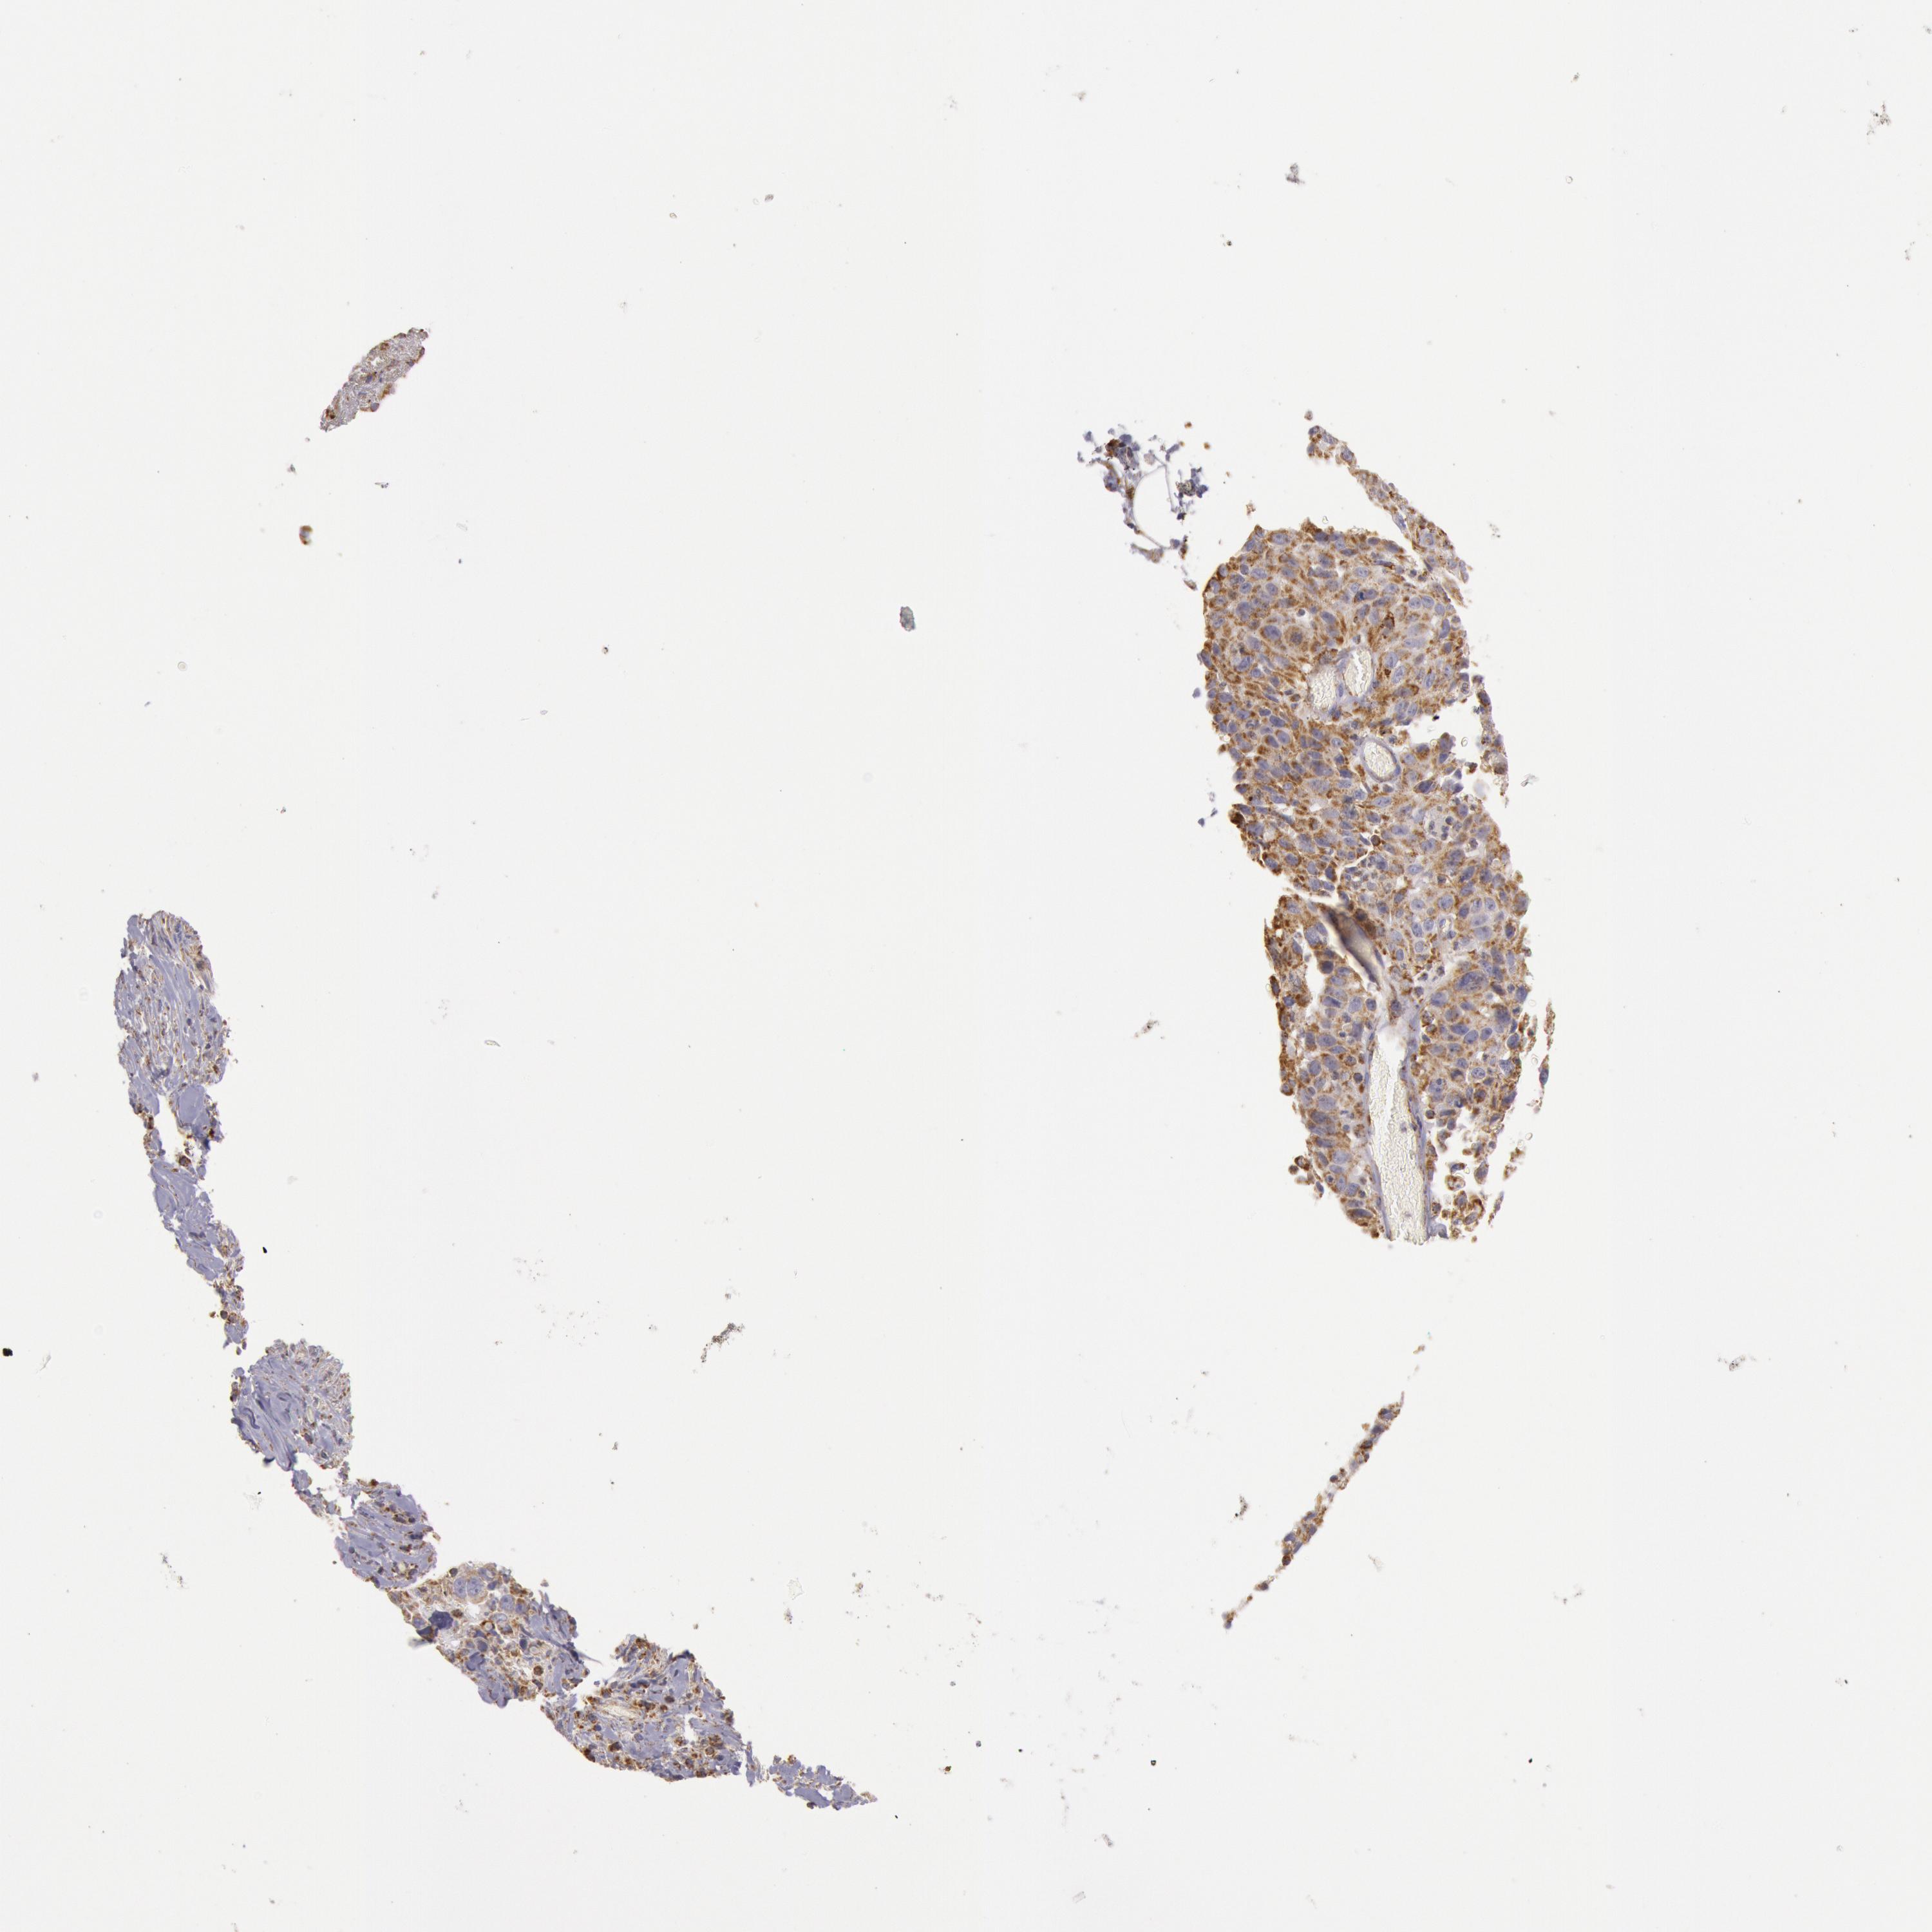

CANCER LUNG CANCER Show tissue menu

LUAD TCGA LUAD VALIDATION LUSC TCGA LUSC VALIDATION PROTEIN LUAD CPTAC PROTEIN LUSC CPTAC PROTEIN EXPRESSION

ANTIBODIES

AND

VALIDATION